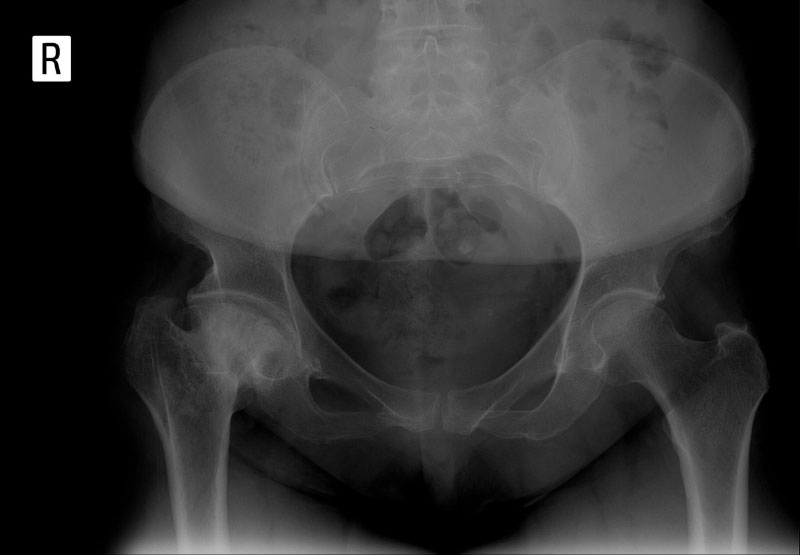

Giai đoạn 1 – Nghi ngờ: Khoảng cách các khớp thu hẹp, hình thành các gai nhỏ xung quanh khớp.

Khoảng cách các khớp

Khoảng cách khe khớp hẹp, gai xương bắt đầu xuất hiện

Gai xương khớp hẹp khe khớp